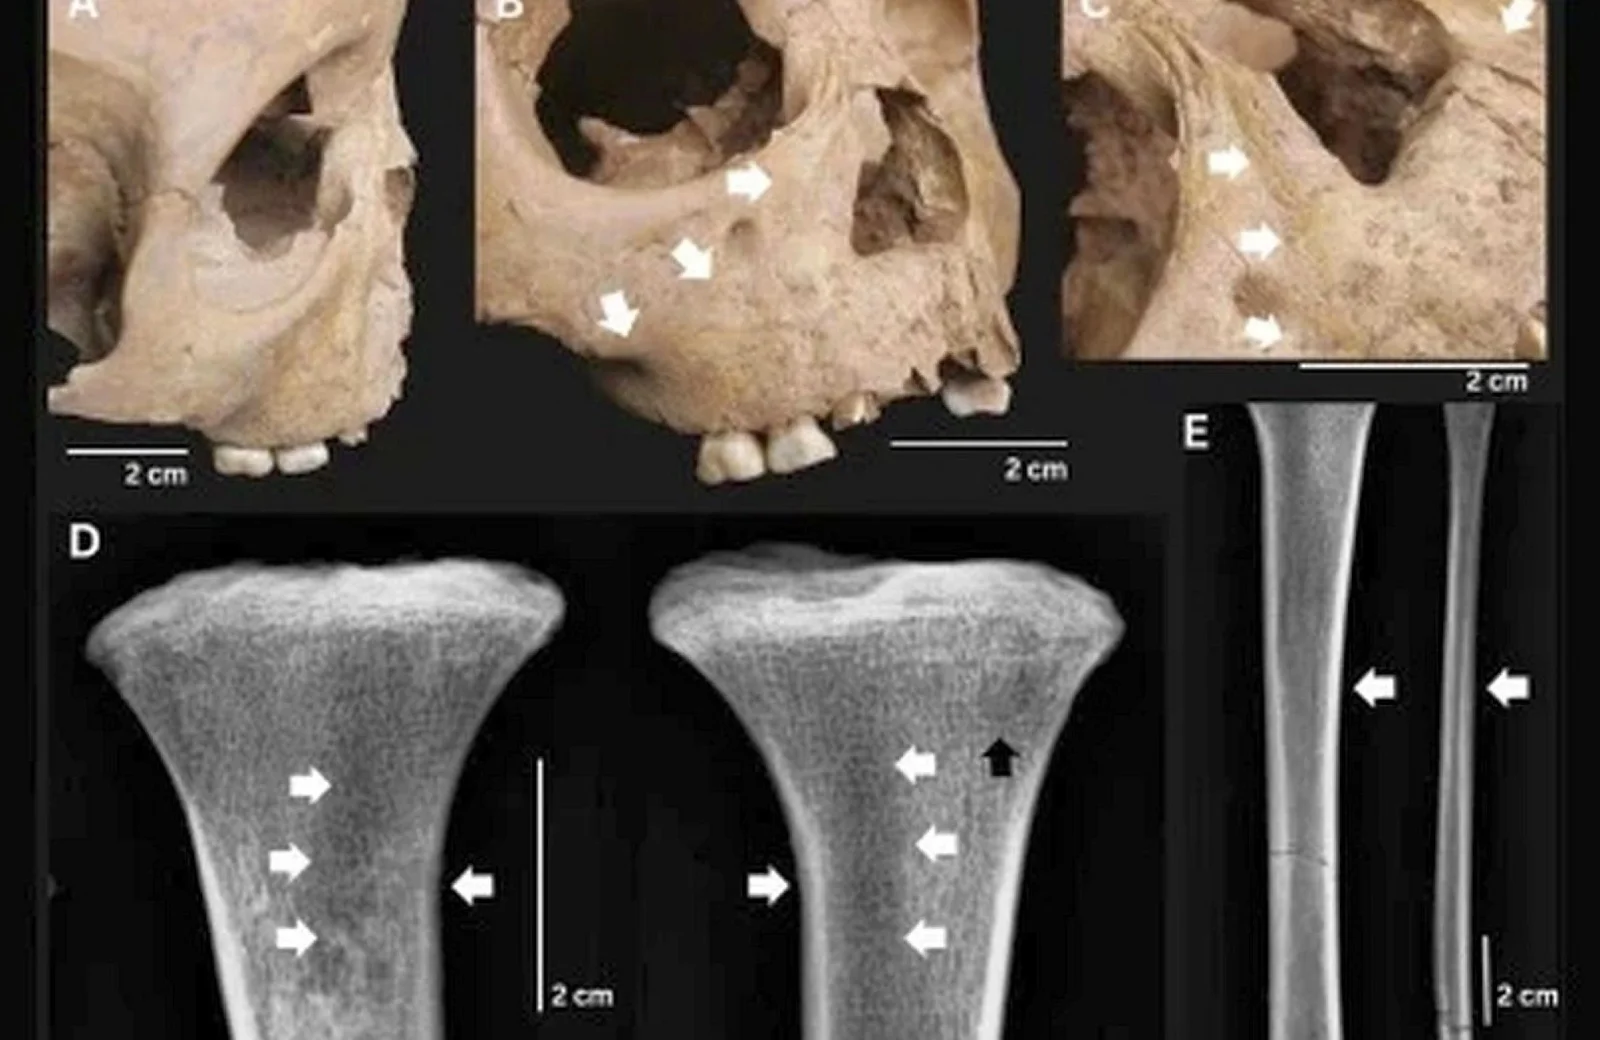

Одному ребенку на момент смерти было всего 18 месяцев — его скелет обнаружили на территории археологического памятника Ман-Бак на севере Вьетнама. Он жил примерно 4−3,5 тысячи лет назад. Палеопатологи выявили на большеберцовых костях и правой ключице особые образования, которые являются признаками третичного сифилиса. Также следы болезни были на лобной кости черепа и зубах.

Возраст еще одного ребенка из Ман-Бака — пять лет. Он страдал от схожего заболевания: у него был деформирован нос, на отростках верхней челюсти и берцовых костях разрослась костная ткань. Также он страдал от цинги.

Также ученые исследовали останки, обнаруженные на территории памятника Ан-Сон на юге Вьетнама, принадлежавшие 2,5-летнему малышу, проживавшему примерно 3,8−3,2 тысячи лет назад. На них также были специфические следы болезни, напоминающие те, что есть у современных людей, больных сифилисом.